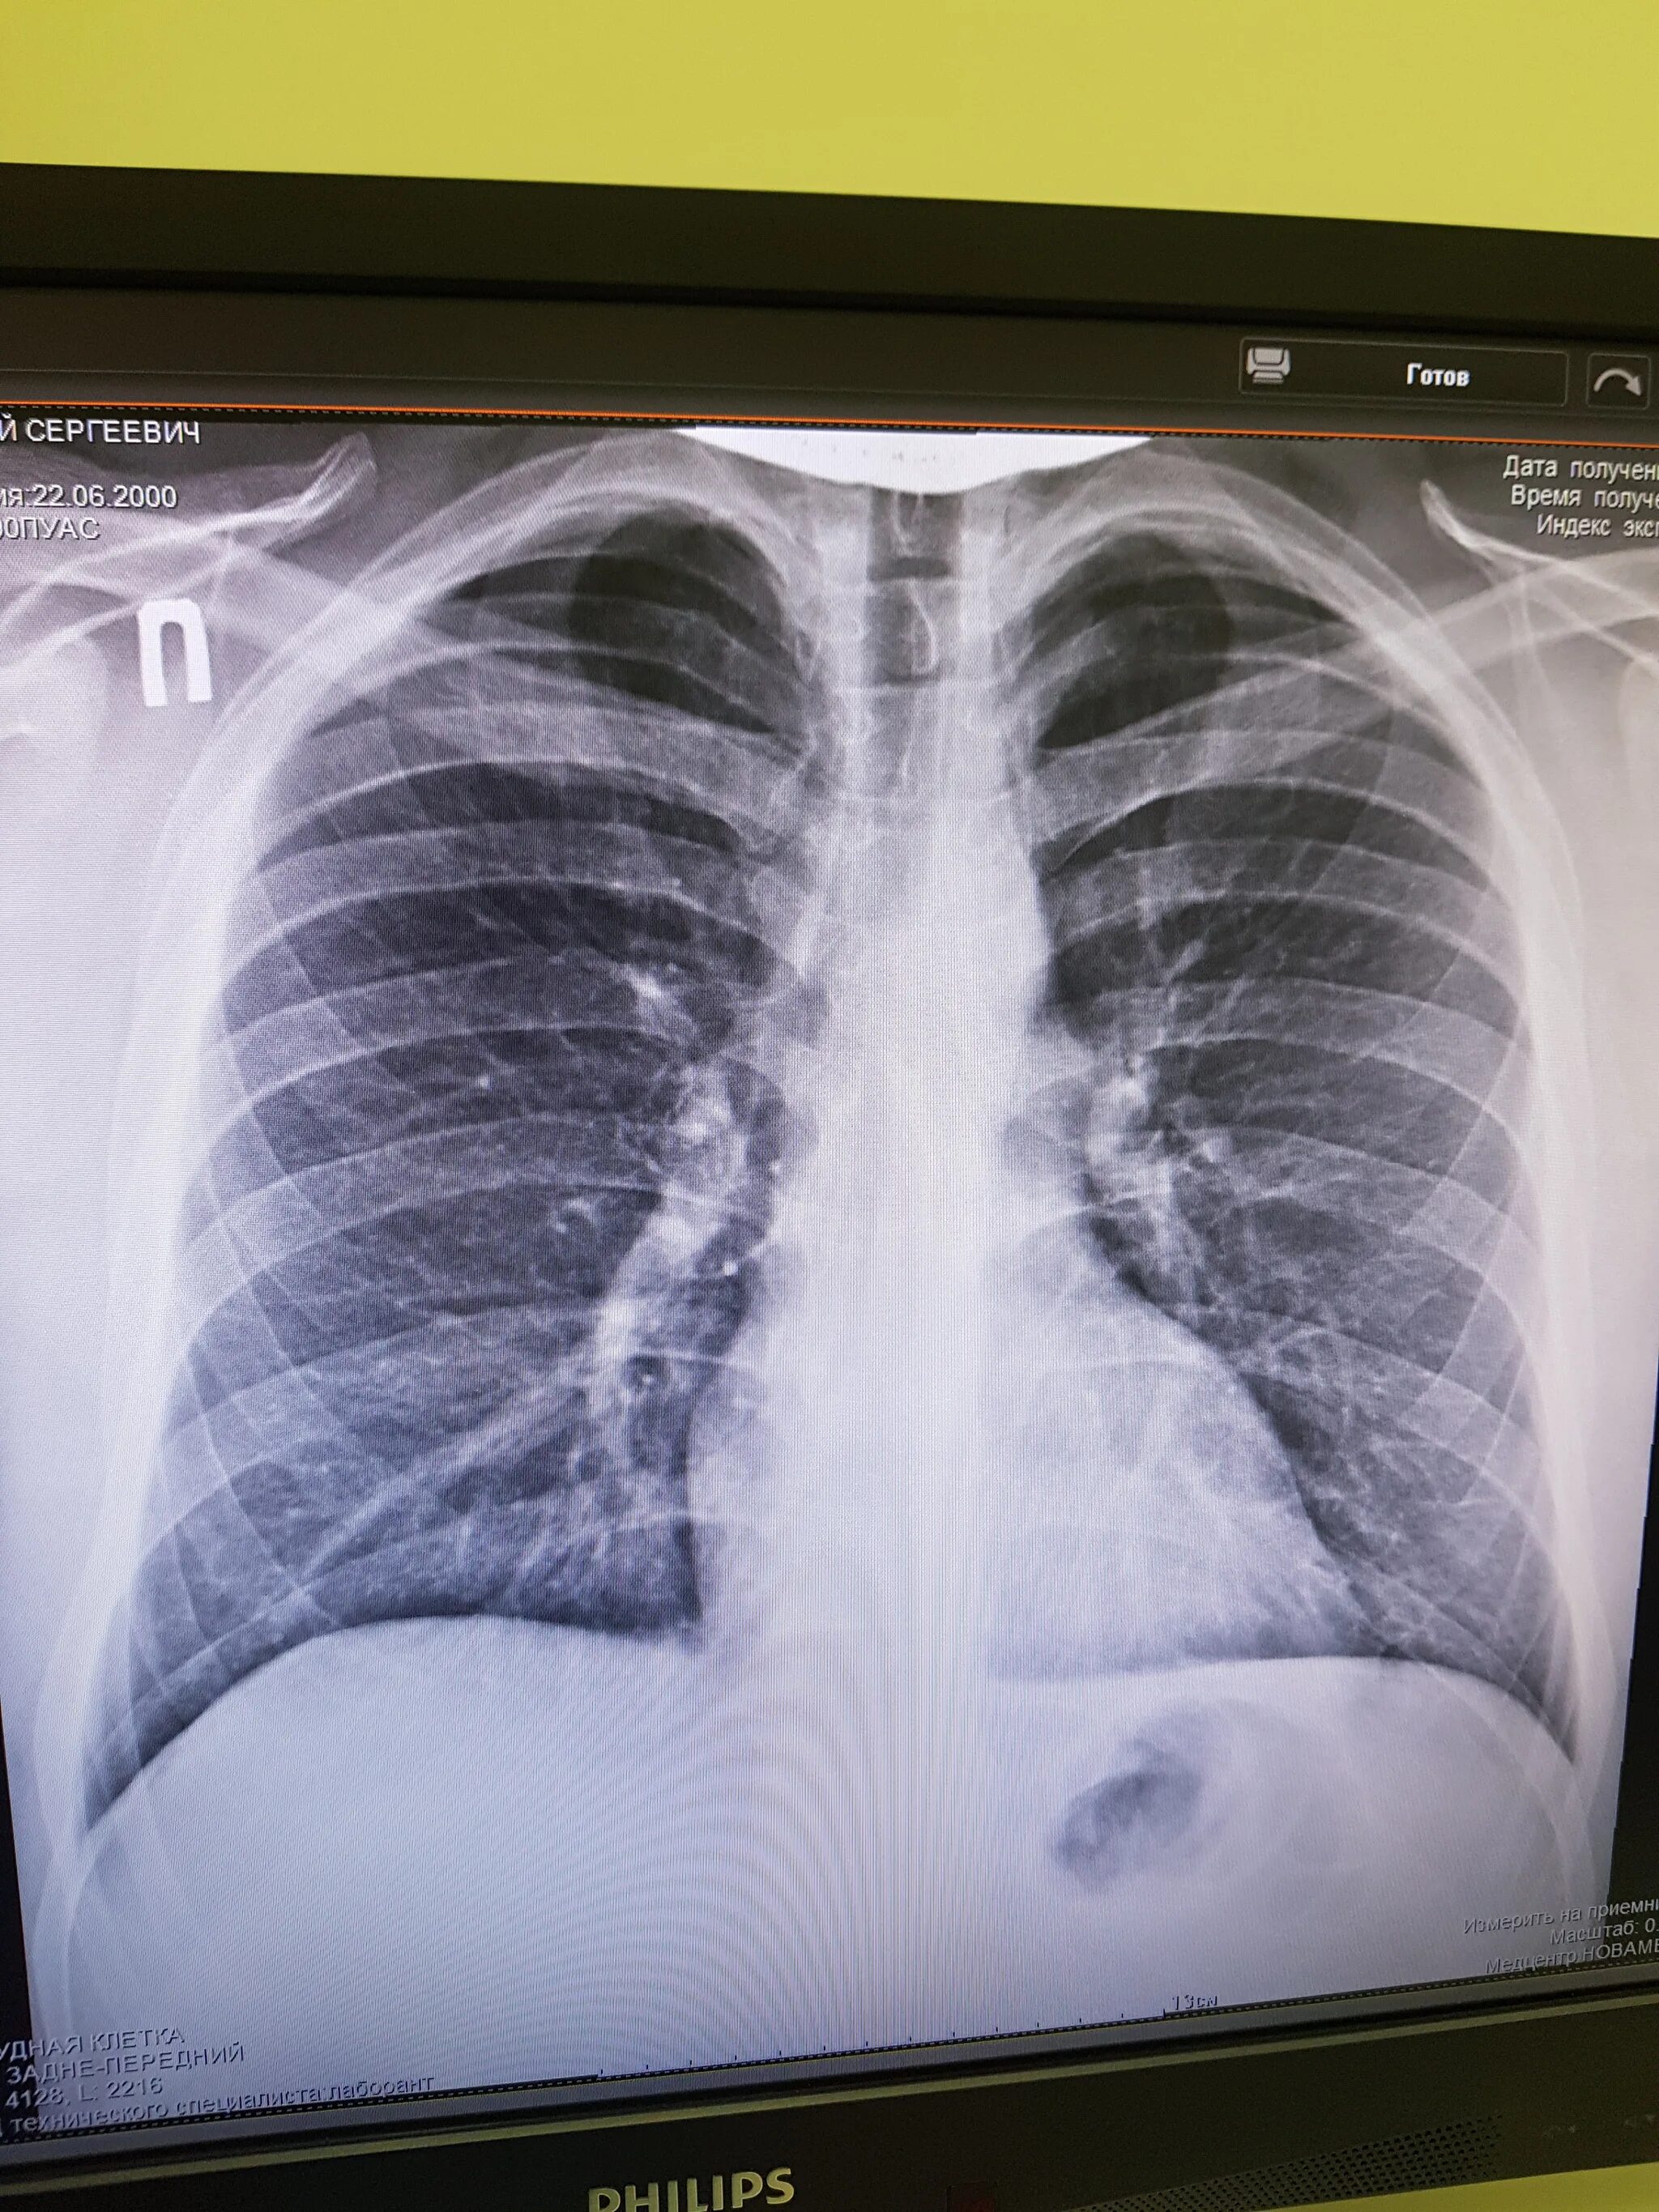

Снимок курильщика